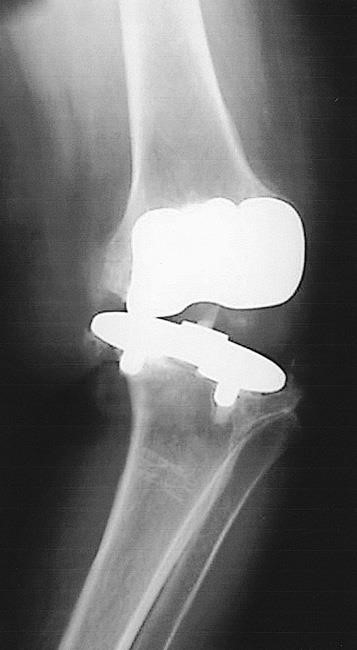

Injured ligaments can make the knee unstable.

If the ligaments around your knee replacement become damaged or improperly balanced (from trauma, inflammatory disease or other reasons), the knee may become unstable or unreliable. As most primary knee implants are designed to work with the patient's existing ligaments, any changes in those ligaments may prevent an implant from functioning properly. This may result in recurrent swelling and the sense that your knee is "giving way." If knee instability cannot be treated through nonsurgical means such as bracing and physiotherapy, revision surgery may be needed to add more constraint to the implants, to compensate for the ligament deficiency.